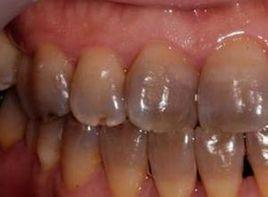

牙齒出現黑綠色沉著,牙齒呈現黃、褐、黑色。

牙齒表面覆蓋著一層牙釉質,呈透明或半透明狀態,其深部為牙本質,呈淡黃色。牙齒的顏色與釉質的鈣化程度有關,鈣化程度越高,釉質越透明,而其深部的牙本質的本色透過其使牙齒呈淡黃色

牙齒顏色異常:因為牙齒表面覆蓋著一層牙釉質,呈透明或半透明狀態,其深部為牙本質,呈淡黃色。牙齒的顏色與釉質的鈣化程度有關,鈣化程度越高,釉質越透明,而其深部的牙本質的本色透過其使牙齒呈淡黃色,牙齒顏色異常見於各種牙病。牙齒出現黑綠色沉著,牙齒呈現黃、褐、黑色。

牙齒表面覆蓋著一層牙釉質,呈透明或半透明狀態,其深部為牙本質,呈淡黃色。牙齒的顏色與釉質的鈣化程度有關,鈣化程度越高,釉質越透明,而其深部的牙本質的本色透過其使牙齒呈淡黃色。